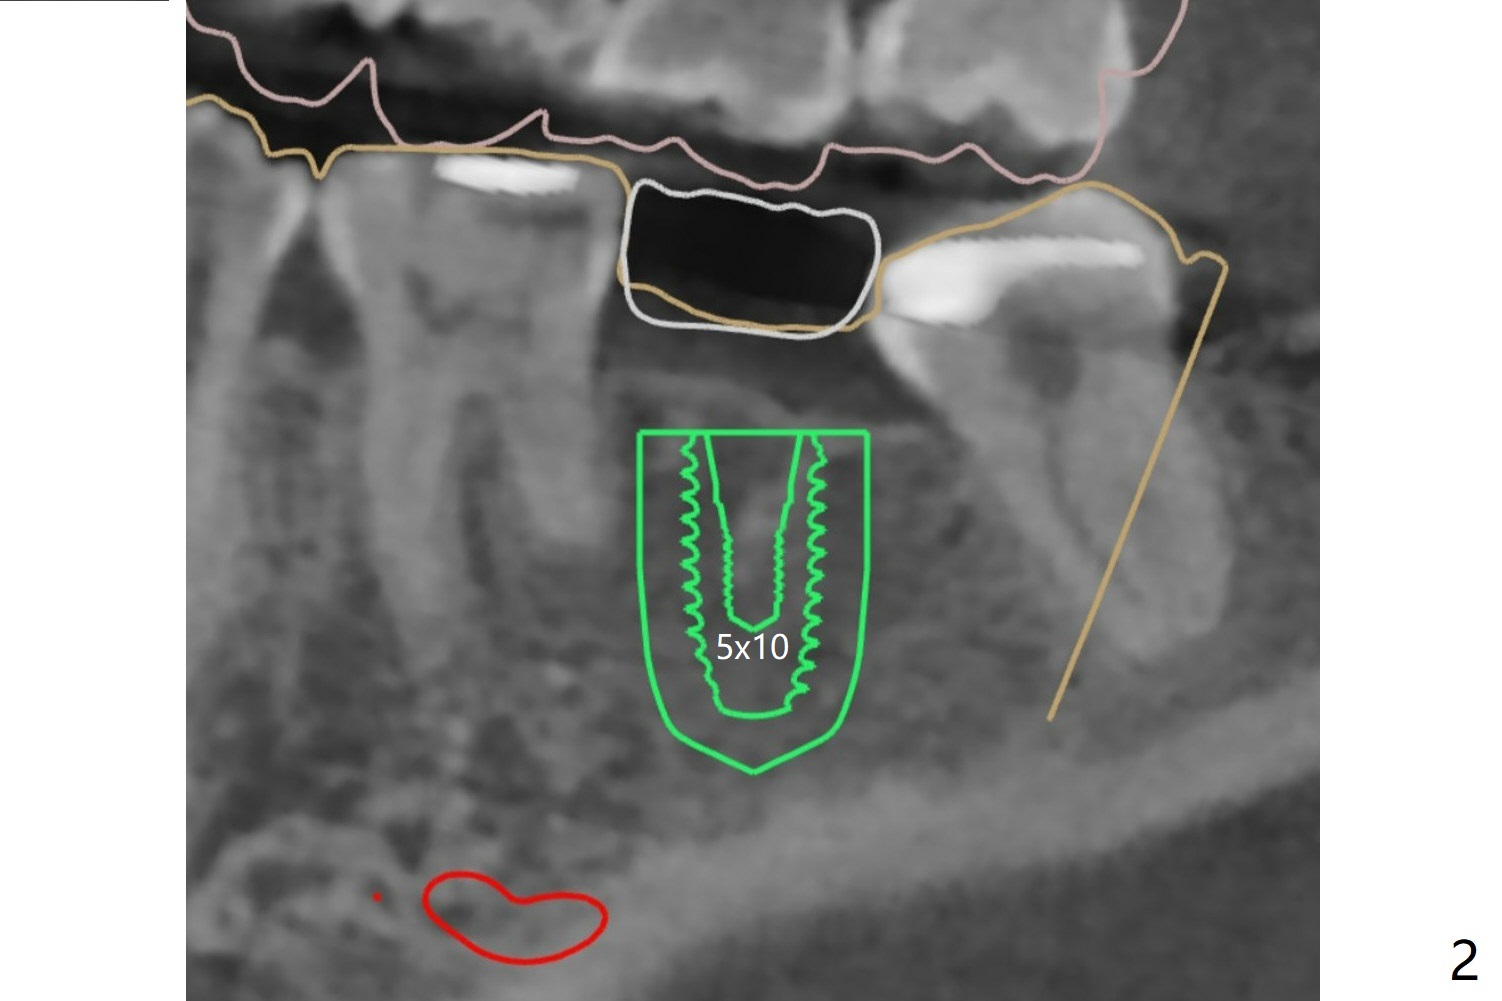

In contrast to #2 implant, the insertion torque of a 5x9 mm implant at #18 (Fig.1) is less than 10 Ncm because of depth difference between 2 implant systems. The design is for 5x10 mm. In fact each drill has its inherent 1.2 mm long tip. The 8.5 mm drilling depth is enough for 9 mm implant. The 2nd potential problem is that the implant may truncate a branch from the Inferior Alveolar Canal to the distal root of the 1st molar (Fig.2 (original design)). Ideally the implant should be placed distal and tilted mesial and short in length (Fig.3 (design to be improved)). A smaller implant may also help. A layer of new bone forms on the top of the implant 3 months postop (Fig.4 *). It is removed with surgical handpiece. After use of 5.6 mm profile drill, a 6x4 mm healing abutment is placed with minimal clearance from the mesial crest (Fig.5 *). A month later, a 5x4(3) mm pair abutment is seated apparently completely (Fig.6). A crown is delivered nearly 6.5 months postop (Fig.7 (mesial contact light)). The implant is subcrestal (*).